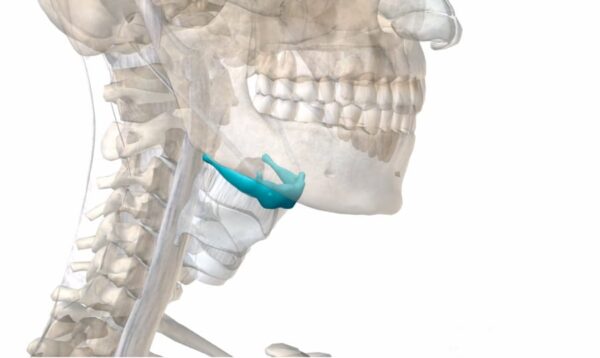

¿Qué es la cintura pectoral?

La cintura pectoral, también conocida como cingulum pectorale, se refiere a la estructura formada por la escápula y la clavícula en el esqueleto humano. Esta región desempeña un papel crucial…